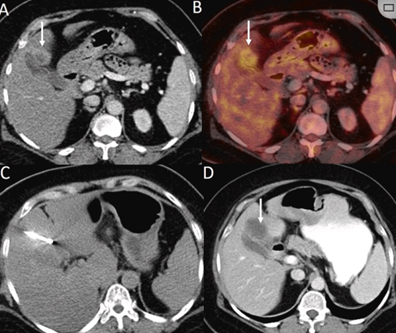

胆囊附近转移灶(来自子宫颈癌)的冷冻消融术

(A)门静脉期 CT 图像显示胆囊附近有病变(箭头)。

(B) PET-CT 图像显示病变处(箭头)。

(C) 手术过程中CT 显示冷冻探针位于病灶内。

(D)消融手术后 1 个月CT 显示完全消融。